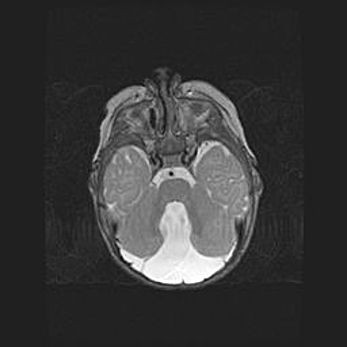

Мальформация Денди-Уокера. Киста задней черепной ямки.

Агенезия мозолистого тела.

Возраст: 2,5 месяца

Вес: 2420 г

Пол: женский

Окружность головы: 37 см

Срок гестации: 32 недели

Мальформация Денди—Уокера — редкий вид патологии ЦНС, представляющий собой врожденный порок развития каудального отдела ствола и червя мозжечка, ведущий к неполному раскрытию срединной (Мажанди) и латеральных (Лушка) апертур IV желудочка мозга. Для этогно синдрома характерна триада симптомов: гипотрофия червя мозжечка и/или полушарий мозжечка, кисты задней черепной ямки, гидроцефалия различной степени. В 70% случаев порок сочетается и с другими аномалиями головного мозга, в частности с агенезией мозолистого тела.